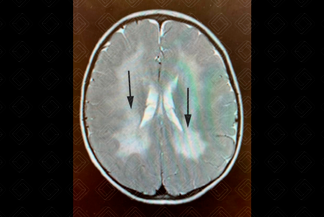

Descrição da imagem: Menino de 2 anos, com desenvolvimento normal até os 4 meses, com subsequente início de quadro de ataxia e desequilíbrio. Ressonância magnética, imagem axial, T2 evidencia padrão tigroide (setas pretas).

• Achados precoces: Redução do sinal em T1 na substância branca profunda; no T2 há um hipersinal confluente periventricular (em forma de borboleta), com preservação de mielina perivenular (padrão tigroide) e, inicialmente, pode haver preservação das fibras em U;